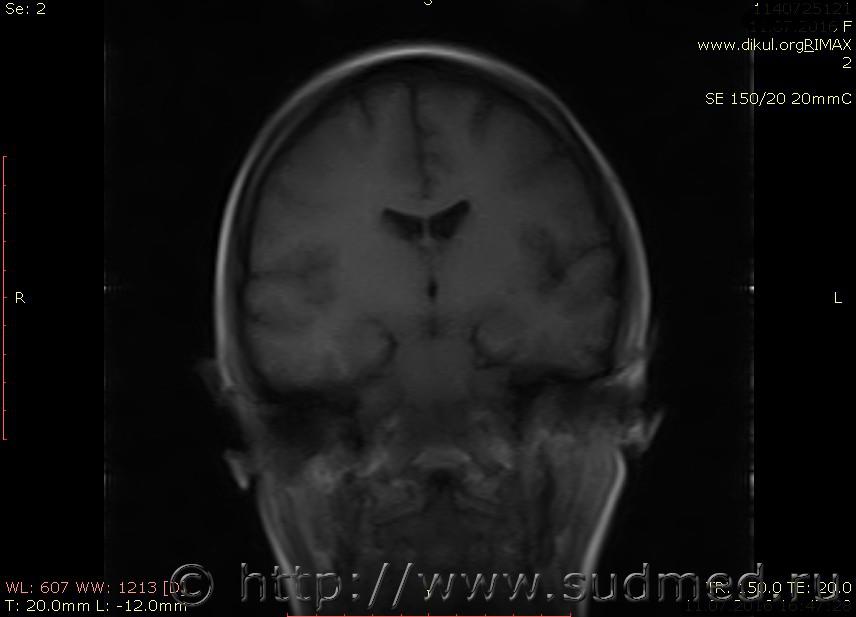

МРТ головного мозга показало: МР-данных за наличие очаговых изменений в веществе головного мозга на момент исследования не выявлено. МР-признаки нарушения соотношения в атланто-осевом суставе. Определяется ассиметрия положения зубовидного отростка С2 относительно боковых масс С1(справа 6,5; слева 4 мм.)

Сама по себе эта информация даёт основания подозревать вывих первого шейного позвонка, но однозначно не свидетельствует о наличии вывиха. Нужно смотреть на снимках наличие реакции со стороны мягких тканей, в т.ч. связочного аппарата, нужно анализировать особенности неврологической патологии, её динамику и проч.

Запрошен электронный вариант снимков из учреждения, где делалось МРТ. Т.к. с самого снимка делать копии не получается,очень мелкие кадры. Завтра попробую вставить в сообщение. (Но СМЭ снимок не смотрел, смотрел только мед.карту, в которой находилось описание МРТ).

Посмотрите пожалуйста снимки, надеюсь на них видны позвонки С1,С2?

Прошу прощения, попробую снова прикрепить файлы. Данные учреждения и пациента убраны.